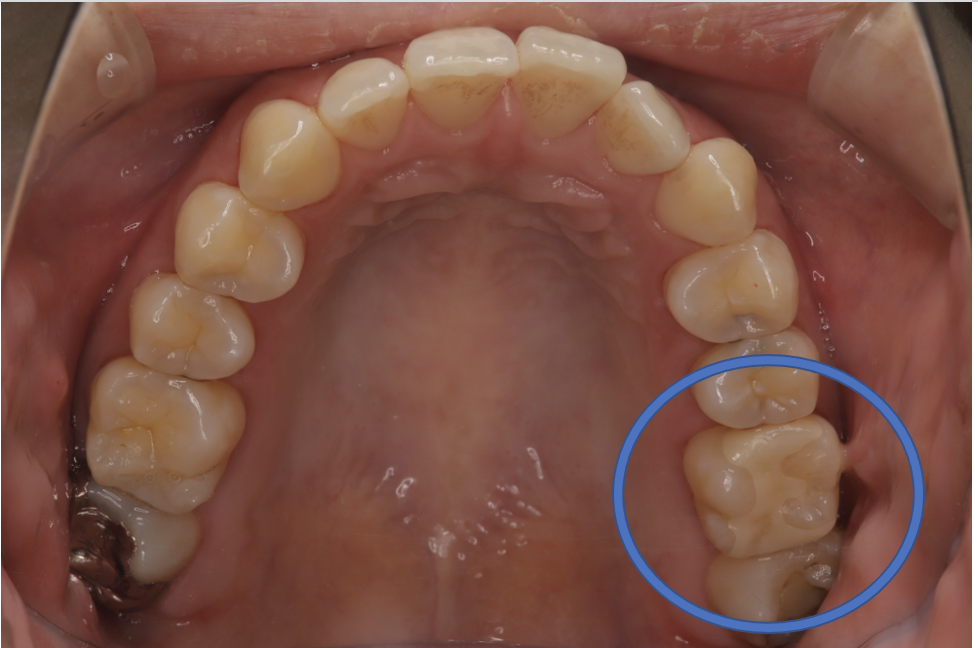

フルジルコニアIn 2 No.34

Before

After

| 治療方法 | フルジルコニアIn 虫歯などで失った歯質を天然歯と同じ色・質感のセラミックの一種であるジルコニア(人工ダイヤモンド)で補う治療法。 |

| 治療のデメリット | 変色がなく耐久性の高い治療ですが、歯周病や二次虫歯を予防するためには歯科医院での定期的なメインテナンスが大切です。 |

| 費用 | ¥69,000 |

| 通院回数 | 1ヶ月〜3ヶ月 |

| 備考 | 院長より 奥歯の、歯と歯の間に虫歯ができているケースでした。詰め物を選ぶ時には、見た目の自然さよりも、噛み合わせが強いことへの対応を重視して、セラミックではなく、強度が強く人工ダイヤモンドとしても使用されるジルコニアインレーを選択することもあります。 |